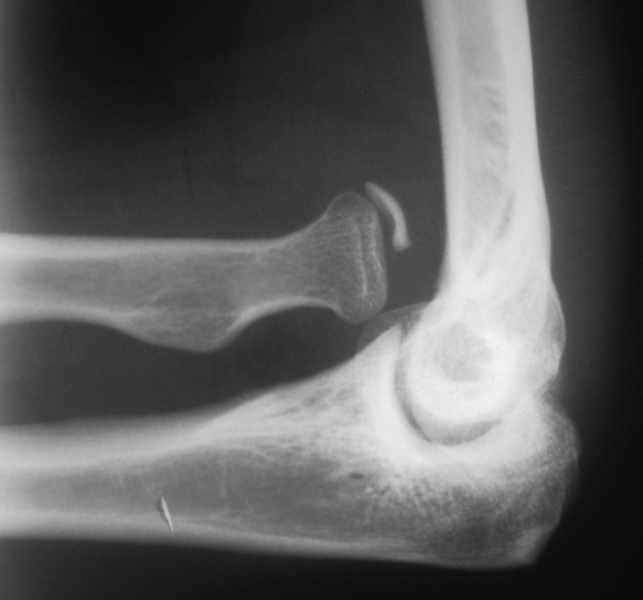

Застарелый вывих лучевой кости |

Мужчина 28 лет. Поступил в отделение по поводу: застарелого вывиха левой лучевой кости. Со слов больного травму получил в 2001 году (предположительно переломовывих Монтеджи). 4 месяца назад начало беспокоить онемение в левой руке, от кончиков пальцев до верхней трети левого предплечья, по утрам. После разминки эспандером, онемение проходит. При осмотре: левая верхняя конечность без видимой деформации. В проекции локтевой ямки пальпируется, выстоящая головка лучевой кости, пальпация безболезненна. Пальцы левой кисти теплые. Чувствительность не изменена. Хотелось бы узнать мнение коллег по поводу тактики лечения такого пациента.

Если функция сустава нормальная и нет грубой нестабильности - либо резекция головки луча, либо вообще ничего. (COO, 11th ed, Chapter 58 – Old Unreduced Dislocations)

согласен. Я - за резекцию, так как есть неврология. было бы очень неплохо, если бы Вы подробнее поисали характер онемения